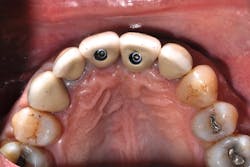

Author Gary Morris, DDS, tracked the paradigm shift from cement- to screw-retained implant restorations in his clinical prosthodontic practice. This was directly related to the introduction of angled implants (Co-Axis Implants, Southern Implants; figure 1). Co-Axis Implants were designed with angle offsetsGrowth of simultaneous extraction and molar implant placement

Anatomical constraints at implant sites often present a conflict between surgical and prosthodontic prerequisites for screw-retained implant-supported prostheses. Howes published the use of a dual-axis implant designed to help clinicians overcome these challenges by facilitating accurate surgical placement and prosthetic simplicity, as well as improved biomechanics and enhancedSince the authors have adopted accelerated treatment protocols with site-specific implants, they both have noted increased acceptance rates, as well as growth in implants placed and restored. Table 6 illustrates the increased acceptance rate for implant treatment in both practices. Data reflects patient acceptance of implant treatment at the first consultation/clinic visit.